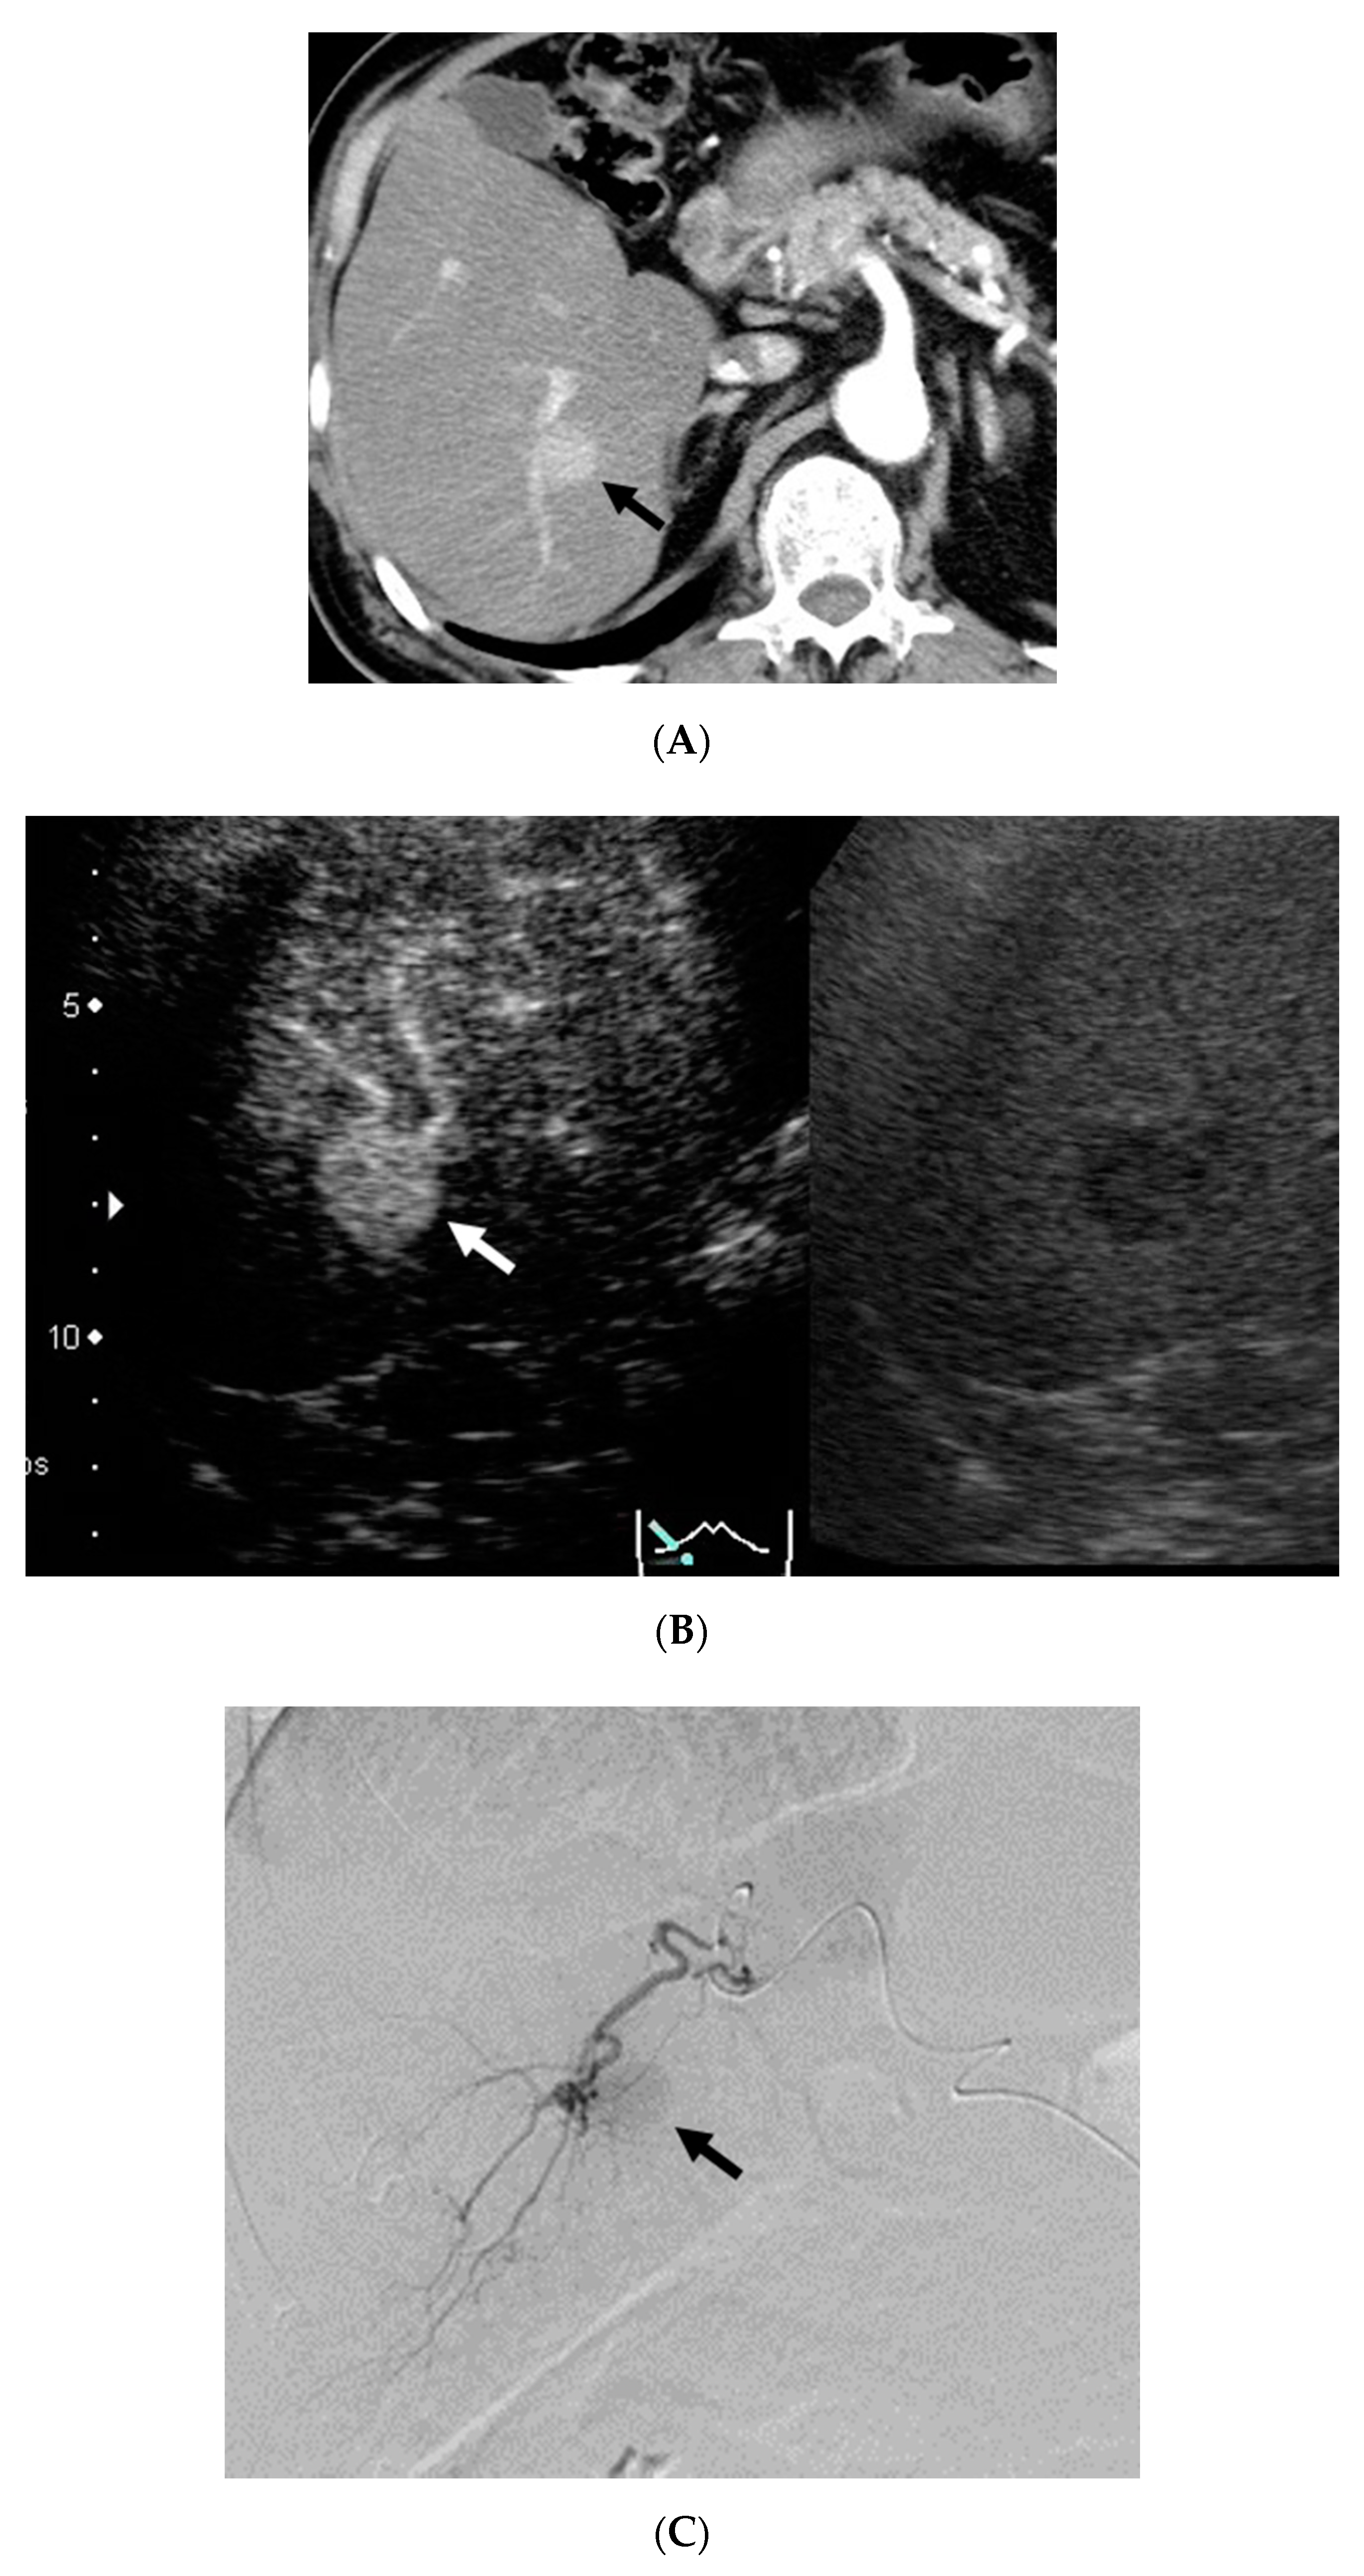

2.2. CEUS Imaging

2.3. CECT Imaging

2.4. DEB-TACE Procedure

2.5. Image Analysis